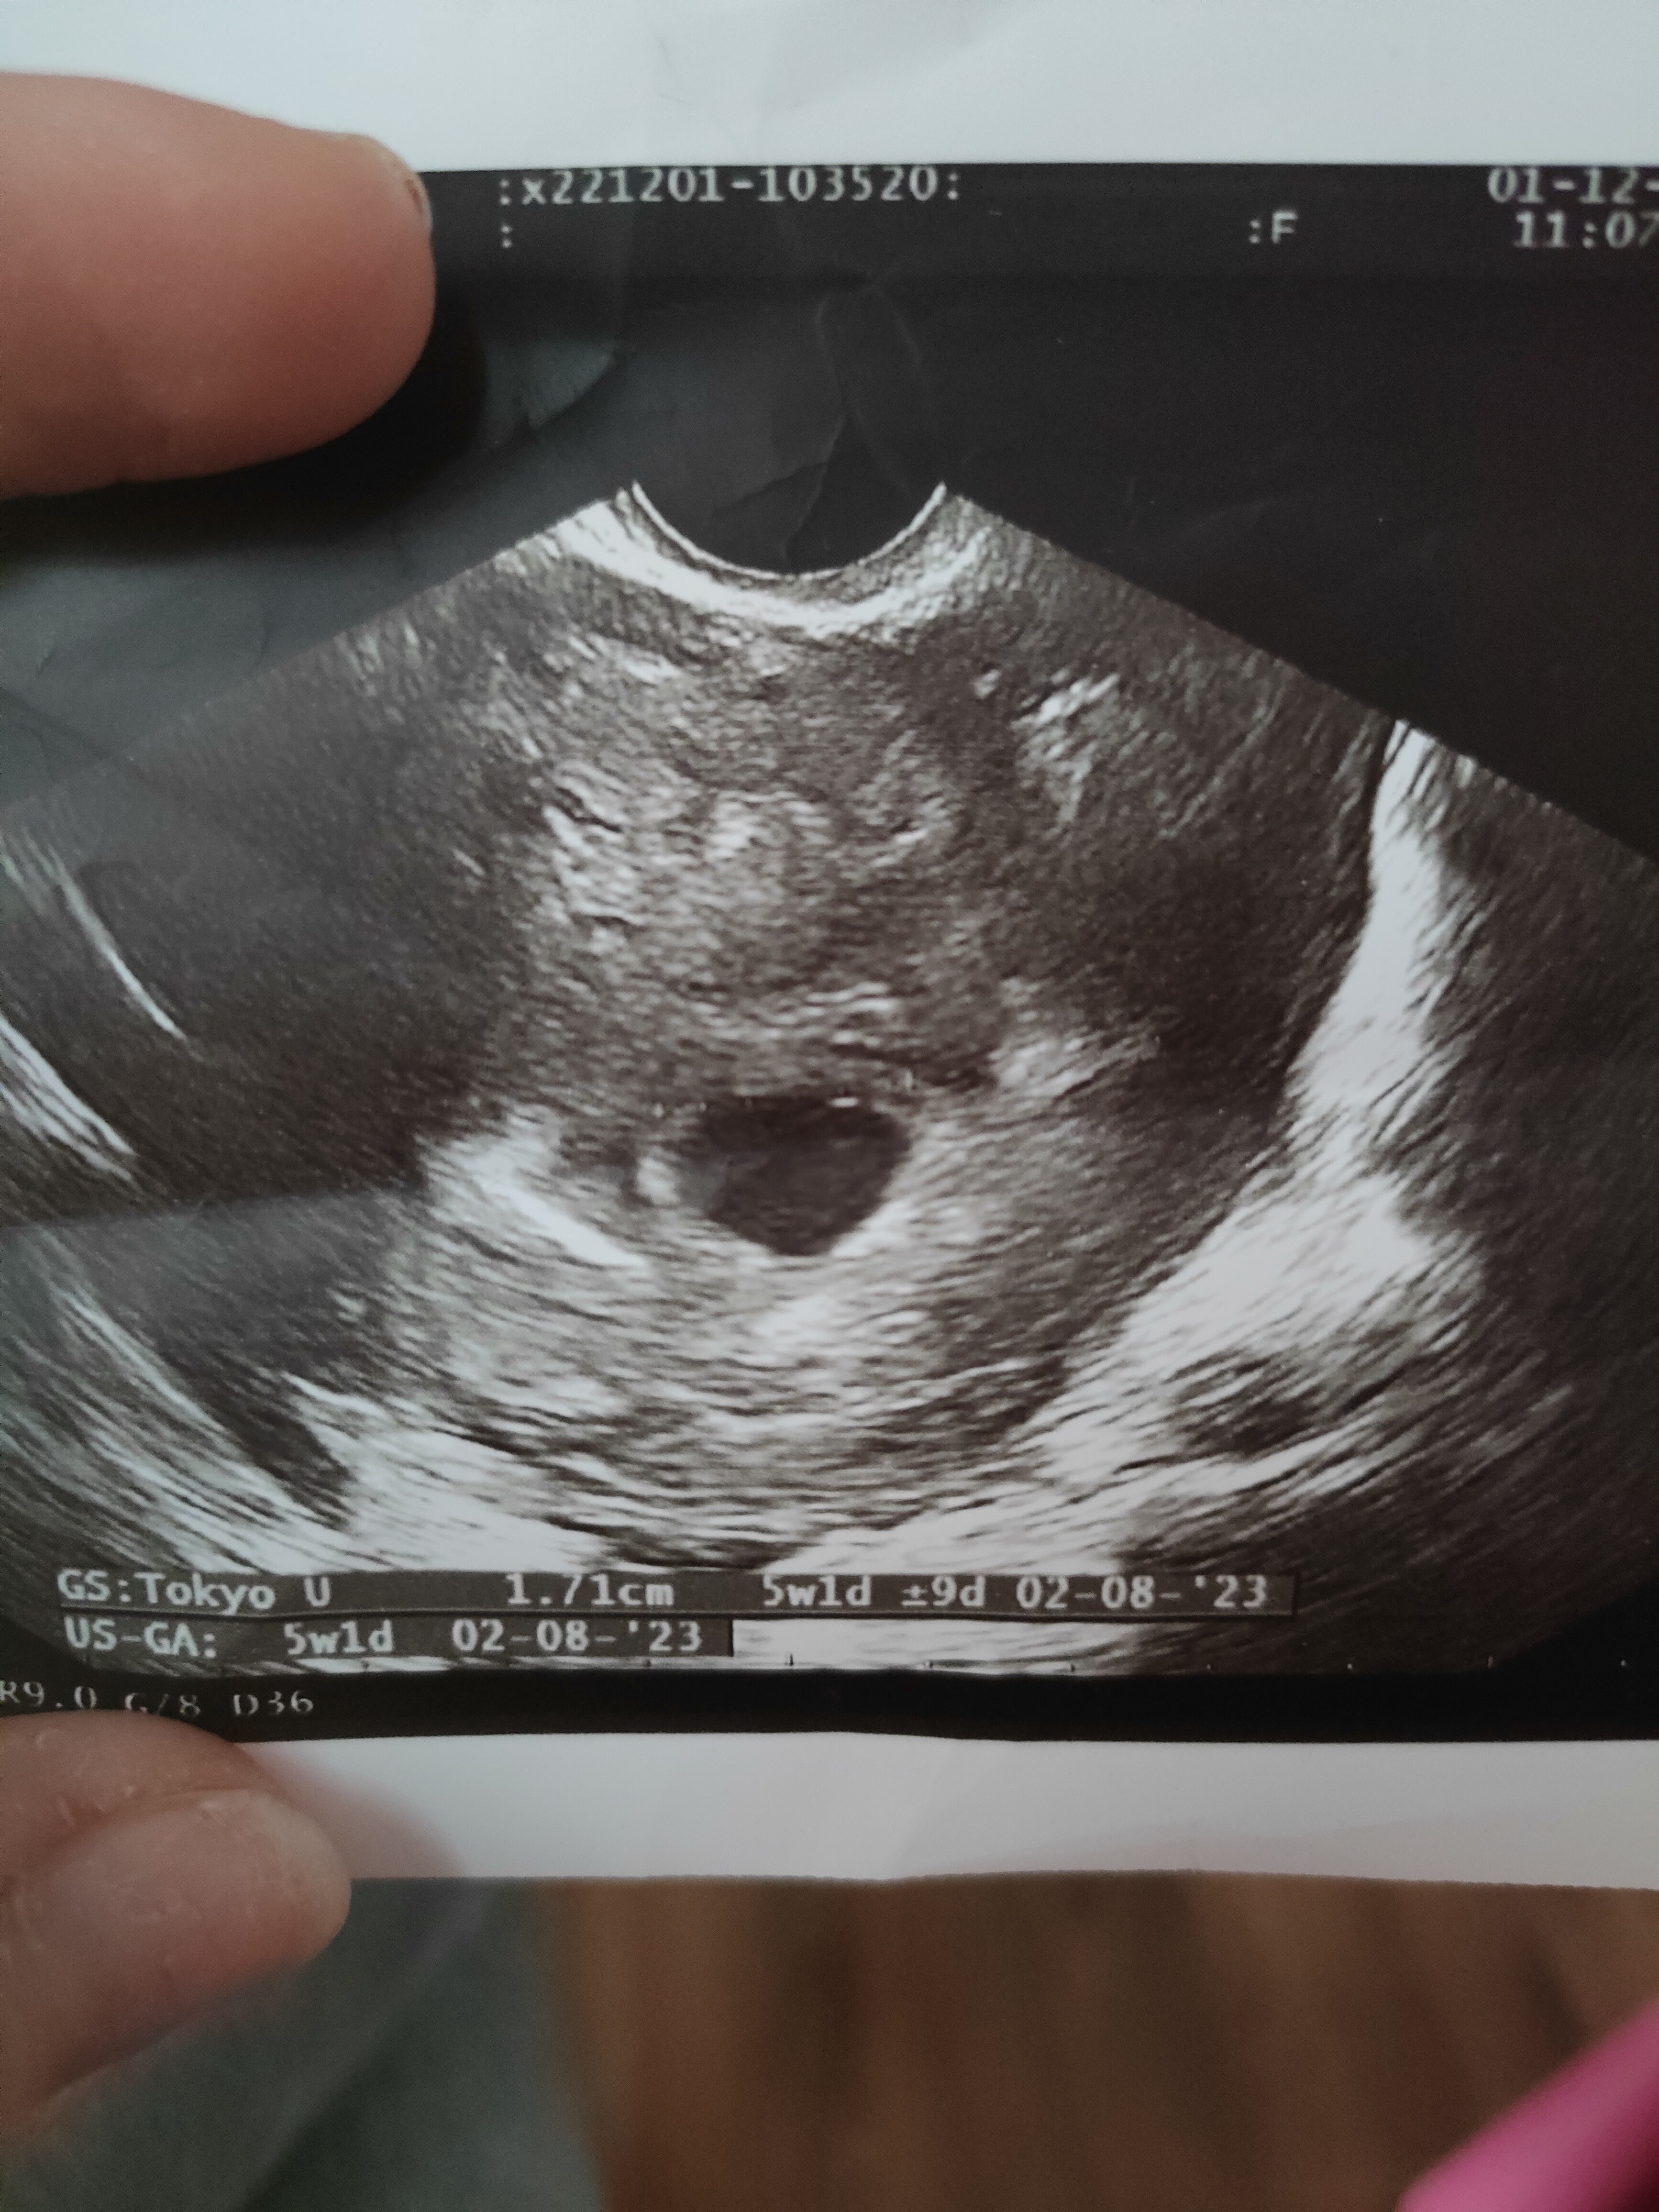

Pusty pęcherzyk

Hej dziewczyny , siostra dziś była u lekarza wg niej jest to 6 +5 i jest póki co sam pęcherzyk tak jak widzicie na zdjęciu. Lekarz powiedział żeby przyszła za tydzień i powinien już być zarodek . Okres miała 1.10 - 16,17,18 wtedy były zbliżenia. 3.11 wyszedł już test ciazowy cień cienia . Co myślicie ? Czy jest szansa ze pojawi się zarodek ?

Kurcze ja dziś byłam u gina i mam z USG 5 tydz ciąża jest młodsza niż miesiączka pęcherzyka ma 1.71 cm ... Wydaje mi się że pęcherzy jest za duzy

Ja miałam pęcherzyk 16 mm i było puściutko i lekarka już wtedy mówiła ze puste jajo choć kazała poczekać jeszcze kilka dni . Wtedy na usg to wychodziło jakiś 6+2 . Jak na 5 tydzień to faktycznie twój pęcherzyk wydaje się duży , było w nim coś już widac ?

Lekarz z byt dużo nic nie mówił .. kazał przyjść za 2 tyg

Tyle że ten sprzęt jest straszny i umówiłam się prywatnie na środę

• IMG20221201120352.jpg

IMG20221201120352.jpg

2,7 MB · Wyświetleń: 125